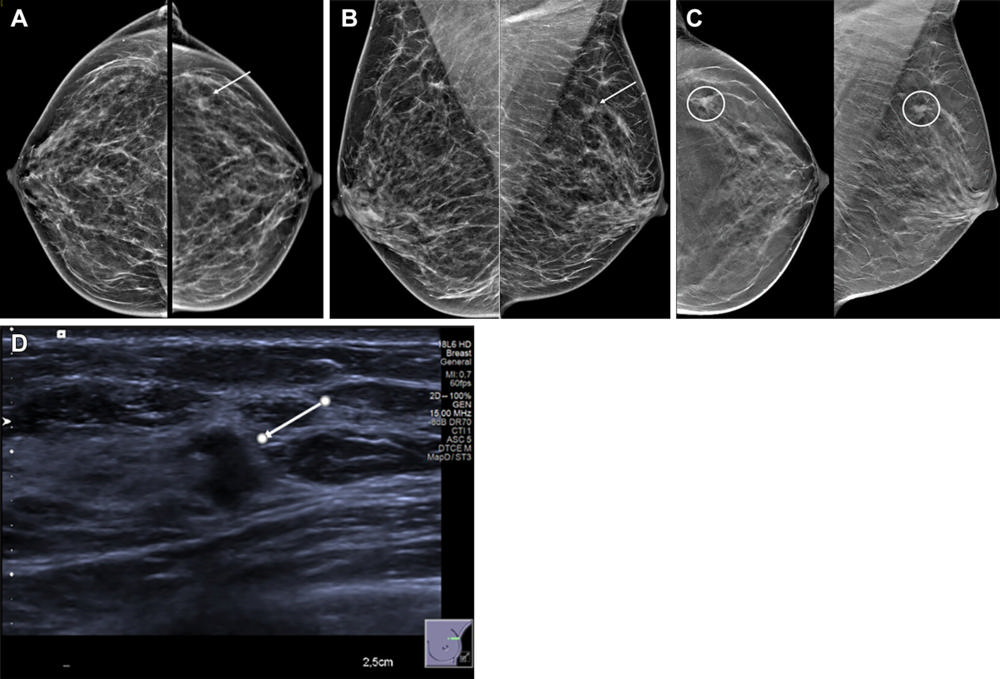

Figure 4. Images in a 54-year-old woman show a palpable lump in the right breast and an irregular mass in the left breast. Mammographic evaluation of the right breast was normal. (A, B) Craniocaudal (A) and mediolateral oblique (B) views of synthesized mammograms and (C) tomosynthesis image in craniocaudal and mediolateral oblique view of the left breast show an architectural distortion with mass (arrow in A and B, circles in C). (D) Targeted US scan at the site of the incidental finding shows an 8-mm hypoechogenic irregular solid mass with indistinct margins (arrow). US-guided biopsy showed invasive ductal carcinoma, grade I.